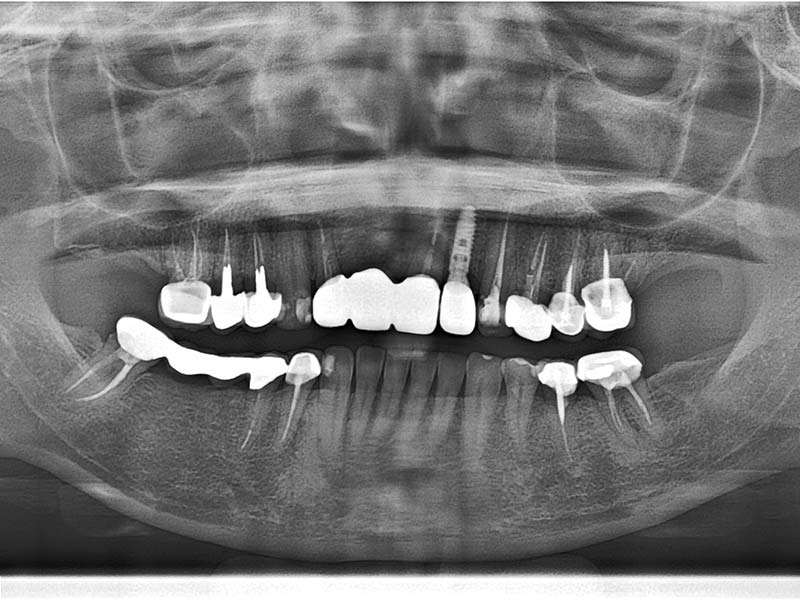

術後成果

治療前

治療後